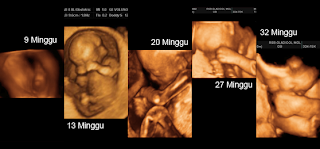

Contoh hasil usg 2d 3d dan 4d. Pada tahun 1970untuk mendapat. Berikut ada contoh hasil usg 5d 4d dan 3d proses perkembangan pertumbuhan janin bayi dalam kandungan usia 1 9 bulan mulai dari pertumbuhan sejak bertemunya sel telur dengan sperma hingga siap lahir gambar disamping adalah hasil usg dan pencitraan lain yang berhasil direkam. Berikut rangkumannya untuk parents. Pada dasarnya hasil dari usg 2d hanya berupa gambar hitam putih saja. Usg 4d memberikan gambar yang bisa bergerak seperti film misalnya bayi menguap mengisap jempol dan sebagainya. Perbedaan hasil usg 2d 3d dan 4d.

Gambar pada hasil cetakan usg 2d memberikan bayangan bentuk janin dan area sekitarnya di dalam rahim. Doppler usg juga dikembangkan dengan mengkombinasikan pindai dan pindai berwarna. Sementara usg 4d dapat menyajikan gambar bergerak seperti anda sedang. Berbagai gambar 2 dimensi dibawah ini juga bisa kalian jadikan sebagai status whatsapp instagram foto profil facebook atau dijadikan sebagai wallpaper handphone kalian. Tidak ada gambar hidung wajah dan semua bagian tubuh dengan jelas. Namun hasil gambar usg 3d dan 4d memiliki perbedaan.

Usg 3d menyajikan gambar yang tidak bergerak diam. Seiring dengan perkembangan teknologi alat yang semula hanya menghasilkan pencitraan hitam putih dan tak bergerak 2d kini berkembang menjadi dimensi gambar yang utuh usg 3d bahkan bergerak usg 4d. Nah apa kelebihan dan kekurangan dari masing masing jenis usg tersebut serta kapan kita membutuhkannya. Hello health group dan hello sehat tidak menyediakan saran medis diagnosis maupun pengobatan. Hasil usg yang paling dominan terlihat adalah gambar janin. Dengan melakukan usg 3d atau 4d anda bisa melihat bentuk mata hidung telinga dan mulut bayi anda lebih jelas bukan hanya seperti gambar hitam putih dalam usg 2d.